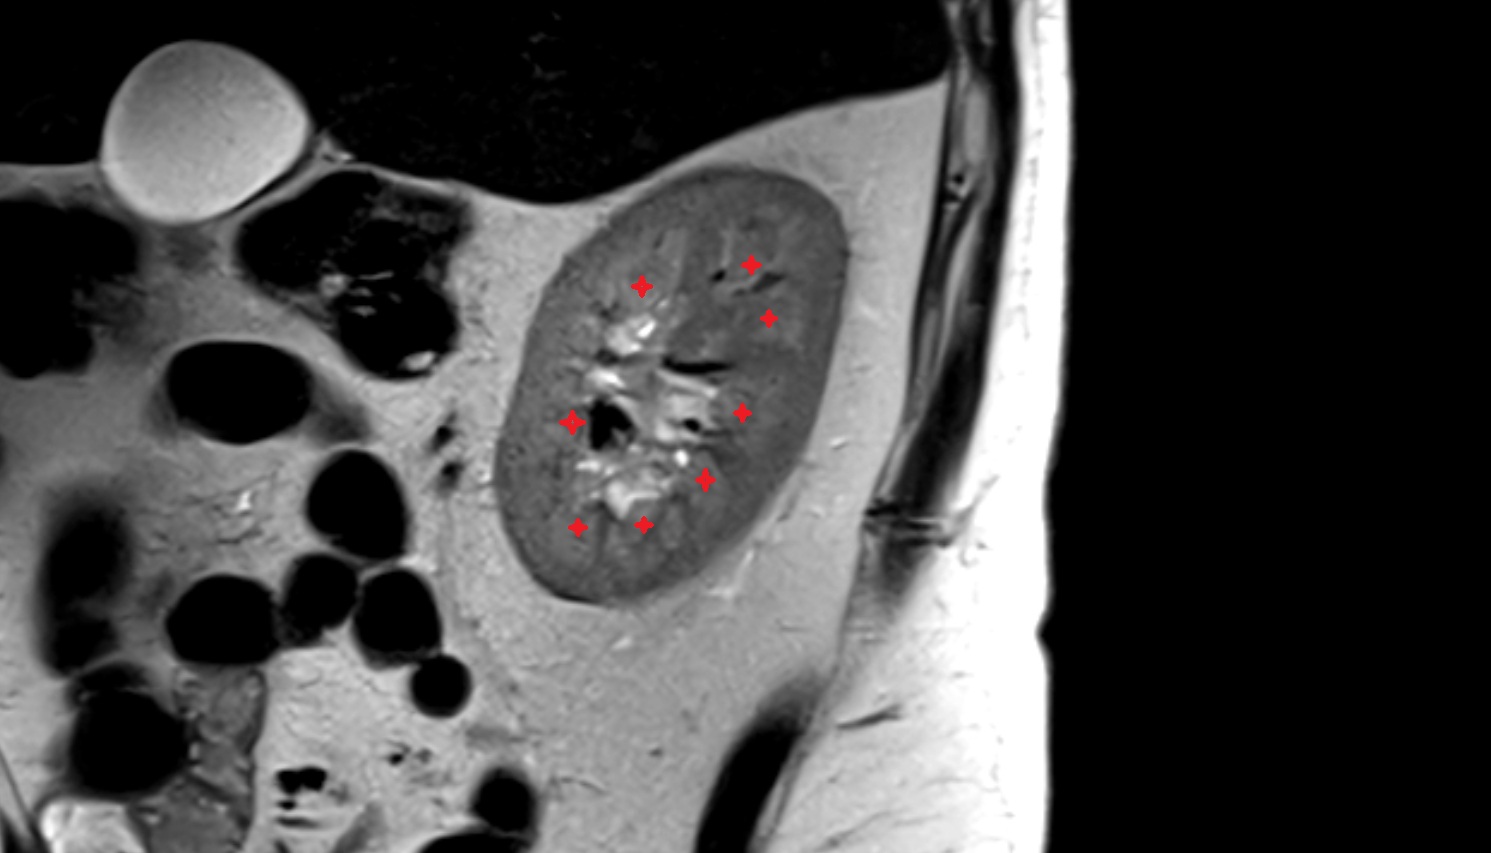

- kidneys

- Right kidney

- Left kidney

- Kidney cortex (Renal cortex)

- Renal capsule

- Renal medulla

- Renal pyramids

- Renal pelvis

- Ureteropelvic junction